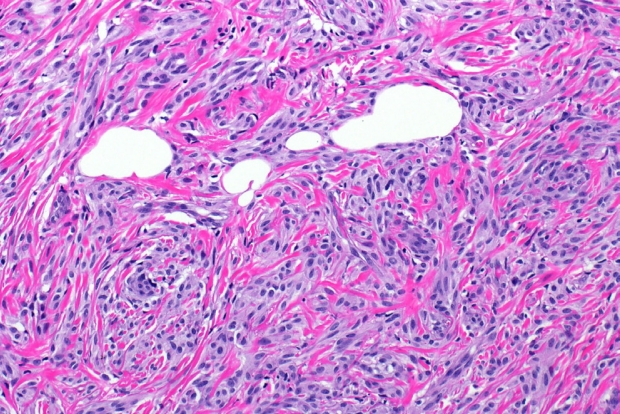

- Microscopically, breast schwannomas are well-circumscribed or encapsulated and can have prominent nodularity (Fig. 3A). Classic schwannomas have a bland spindle cell proliferation with various degrees of anisonucleosis, and wavy, elongated nuclei with tapering ends. These are arranged in parallel rows (nuclear palisading), also known as Verocay bodies (Fig. 3B). There is an abrupt transition between hypercellular (Antoni A) and hypocellular areas (Antoni B) (Fig. 3C). Antoni B areas have loose and myxoid stroma (Fig. 4A). Other key features to schwannomas include numerous small to medium sized vessels with prominent hyalinization and thrombi inside the lumen (Fig. 4B) and may also contain areas of hemorrhage or hemosiderin deposition [3,19].

Fig. 3.Excision of breast schwannoma with nodularity (A), Verocay bodies (B), and Antoni A and B regions (C).